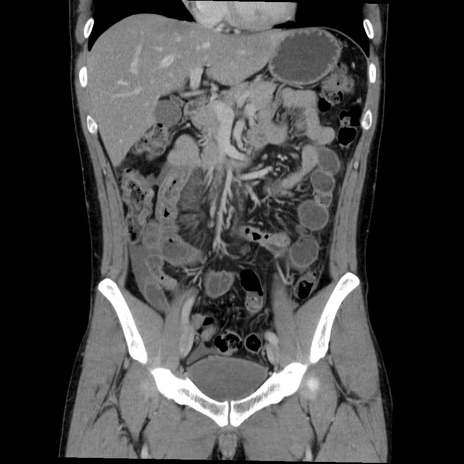

症例36(冠状断像)

【症例】20歳代 男性

【主訴】心窩部痛

【現病歴】今朝より上腹部痛あり。一旦軽快していたが再度出現したため救急要請。昨日夕に白身の魚を含む刺身を食べた。

【身体所見】BP 136/89mmHg、HR 74/min、BT 37.0℃、腹部:膨満、軟、心窩部に圧痛あり。反跳痛なし、筋性防御なし、腸雑音やや亢進あり。

【データ】WBC 17700、CRP 0.48